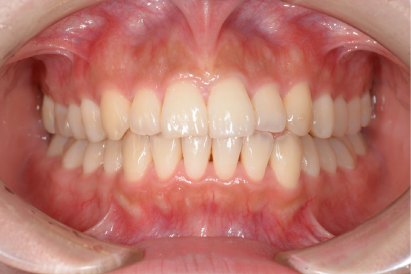

• 症例3

術前

*

術後

年代、性別

10代、女性

職業

学生

主訴

歯並び相談

部位

抜歯を併用してのインビザラインによる全顎矯正

治療期間

2年

矯正費用

95万円

施術説明

前歯が突出感と、下歯がガチャガチャしていることを改善したいということでした。マウスピース矯正は抜歯を伴う矯正は難しいという意見もありますが、適切に診査・診断を行い対応すれば問題ありません。本症例では、上下2本ずつ合計4本の抜歯を行い、スペースを作ることで、上記の問題を矯正で改善しました。非常に綺麗な歯並びになり、非常に喜んでもらえました。

副作用・リスク

なし